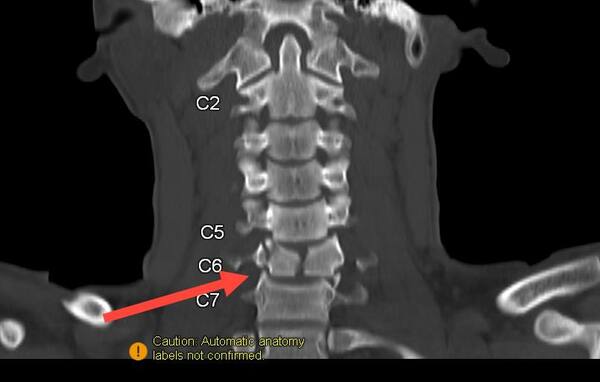

Врачи диагностировали серьёзное повреждение шейного отдела позвоночника. Последствия оказались необратимыми – парень остался глубоким инвалидом, рассказали в ДРКБ.